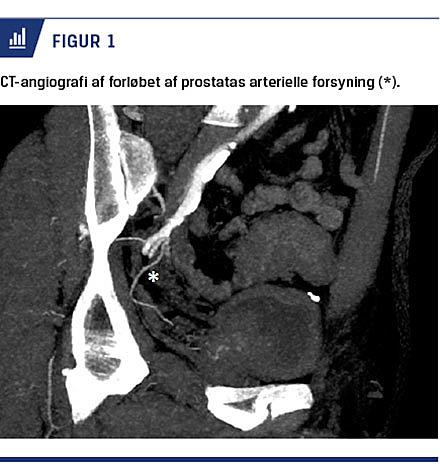

Der er ikke international konsensus om planlægningen af proceduren, men i flere studier anbefales brug af

CT-angiografi (CTA) for at visualisere karanatomien og vurdere eventuelle tekniske udfordringer, som f.eks. okkluderet arteria iliaca interna, udtalt arteriosklerose eller slyngede kar (Figur 1) [18]. Udførelsen af CTA er potentielt forbundet med en risiko for nyretoksicitet på grund af anvendelsen af intravenøst givet kontraststof. Kravet til nyrefunktionen er som for selve proceduren en glomerulær filtrationshastighed > 45 ml/min/1,73 m2 og giver en begrænsning i selektionen af patienter.